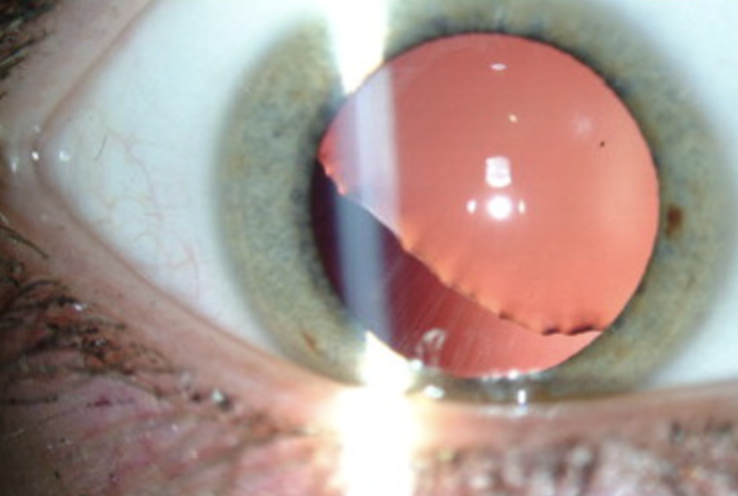

Hyphema

Abnormal findings for iris

Collection of blood inside anterior chamber of eye (space between cornea and iris)

Pooling or collection of blood inside the anterior chamber of the eye (the space between the cornea and the iris); trauma